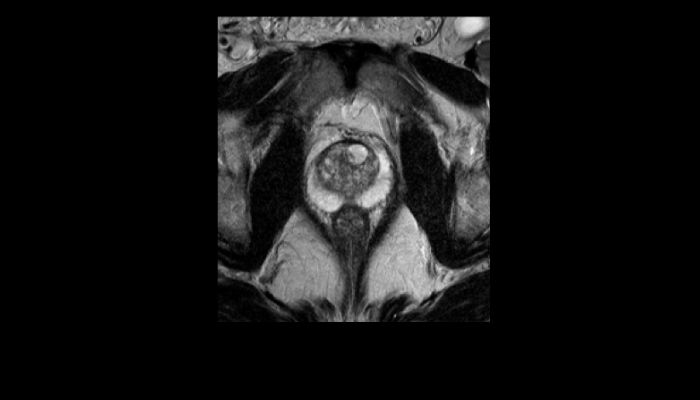

頭部MRI画像 頭部MRI脳腫瘍や脳梗塞、認知症など脳の病気を詳細に評価します。 MRA画像 頭部MRA造影剤を使わずに脳の動脈を描出します。動脈瘤や狭窄を検索します。 脊椎MRI画像 脊椎MRI椎間板ヘルニアや脊柱管狭窄症など脊椎や脊髄の疾患を評価します。 腹部MRI画像 上腹部MRI・MRCP肝臓・胆のう・膵臓・腎臓などの上腹部の重要臓器を詳細に評価します。 乳房MRI画像 乳腺MRIマンモグラフィや超音波と併せて、乳がんを検索や病変の範囲を評価します。 前立腺MRI画像 前立腺MRI前立腺がんを検索します。PSA高値の方はまず前立腺MRIをお勧めします。 子宮・卵巣MRI画像 子宮・卵巣子宮筋腫や子宮体癌、卵巣腫瘍など女性特有の病気を評価します。 膝関節MRI画像 膝関節膝関節の骨や靭帯、半月板を評価します。靭帯断裂や半月板損傷などレントゲンでは評価できない構造も診断できます。 肩関節MRI画像 肩関節肩関節の骨や腱、靭帯を評価します。腱板断裂や腱の断裂などレントゲンでは評価できない構造も診断できます。 心臓MRA 心臓MRA狭心症、心筋梗塞の原因となる冠動脈の狭窄を評価します。造影剤を使用せず、撮影可能です。 DWIBS画像 DWIBS全身のがんを広く検索します。リンパ節や転移の評価にも優れます。